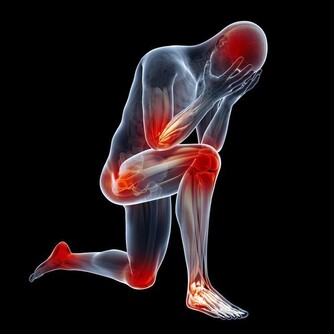

中醫古籍《醫方考》稱:“情志過極,非藥可醫”。不良的精神刺激、自我放大越嚴重,身體垮得越快,最終是自己打倒了自己,可見自我折磨的人最傻。現在很多人們處在緊張和恐慌中生活,身體很受影響。我當醫生這麼多年,癌症病人見得太多了,沒幾個好的,完全好的太少了,都給精神折磨壞了。

有個動物實驗,同樣給兩組老鼠注射癌細胞,給一組老鼠旁邊放一隻貓,另一組老鼠不放。放一隻貓在旁邊,這些老鼠就緊張,身上的腫瘤明顯長得快,就是因為精神緊張容易造成內分泌失調,各方面的生理過程就都不順暢。

人生難免苦難和挫折,生老病死乃自然規律,誰也無法擺脫,有錢難買鬼門關,就看自己是否能正確認識、善待自己。心胸要開闊些,要承認人生多磨難,但世上無難事,思想上能想得開,則沒有過不去的獨木橋。